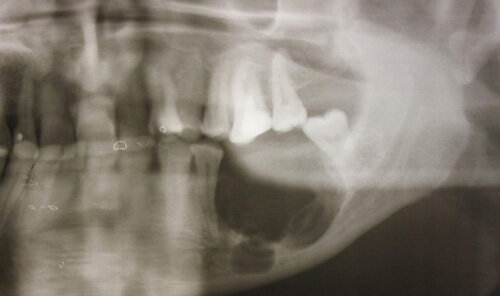

Что касается диагностики, то здесь пациенту делают рентгенологическое обследование. Чтобы вылечить такое заболевание, нужно правильно подобрать антибактериальный препарат, провести десенсибилизирующую, противовоспалительную терапию. Когда наступает период обострения, имеются большие секвестры, то может назначаться хирургическое вмешательство.